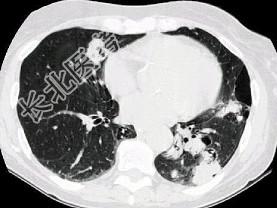

- 单项选择题多发性骨髓瘤患者出现咳嗽,咳痰, 气急,胸片检查发现病变后行CT检查如图, 最可能的诊断为 ( )

A、肺部感染

B、两肺结核

C、骨髓瘤转移肺部

D、肺淀粉样变性

E、肺转移瘤